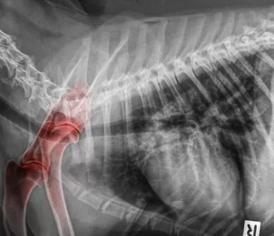

1. 슬개골탈구란?

슬개골탈구는 무릎 뼈(슬개골)가 정상 위치에서 벗어나 바깥쪽이나 안쪽으로 밀려나는 질환입니다.

| Grade 3 | 대부분의 시간이 탈구된 상태, 걸을 때 절뚝거림 |

| Grade 4 | 완전히 탈구되어 고정, 다리를 거의 쓰지 못함 |